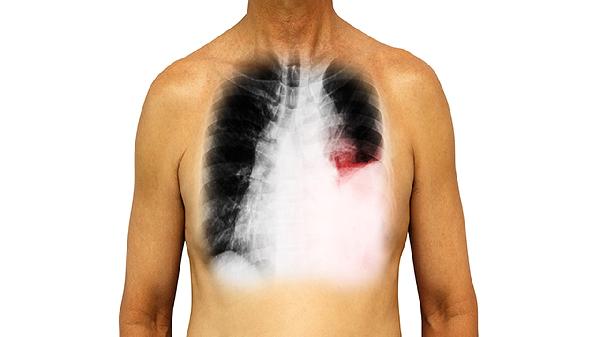

肺部有结节严重吗,如何治疗

肺部结节是否严重需结合结节性质判断,多数为良性无需特殊治疗,少数恶性需手术干预。肺部结节的处理方式主要有定期复查、抗感染治疗、穿刺活检、手术切除、靶向治疗等。